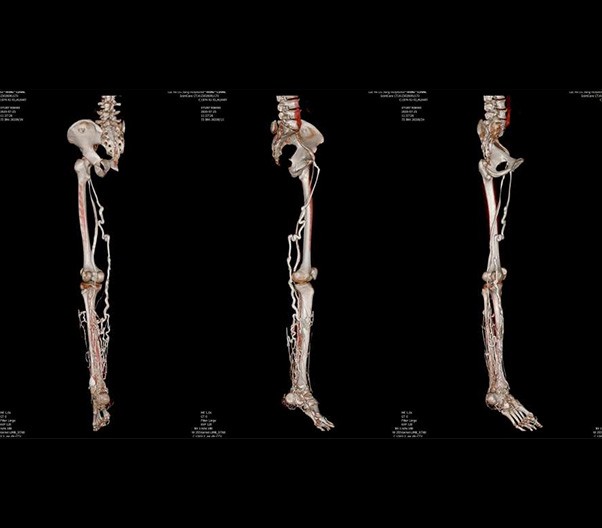

The 1024-pixel image matrix brings superior image clarity (0.6 mm slice thickness) and stimulates the early detection of small lesions, thus improving diagnostic reliance.

ScintCare CT 16 incorporates an entirely digital integrated ScintiStar detector, which was solely developed by MinFound, from material to the whole structure design, based on the technical know-how of our skilled scientific team. The system produces high-resolution images with a low radiation dose and an excellent signal-to-noise ratio.

臨床畫廊